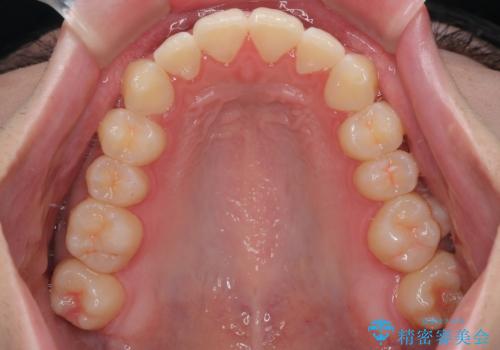

診察してみると、下の前歯が並ぶためのスペースが足りないことが、歯並びがデコボコしている原因でした。

そこで今回は、以下の2つの方法を組み合わせて治療を行いました:

下の前歯の歯と歯の間をわずかに削ってスペースを作る(IPR)

奥歯を後ろに動かして、前歯が並ぶためのスペースを確保する

この計画により、デコボコだった下の前歯はしっかりと並び、わずか1年で治療を終えることができました

見た目が気にならないマウスピース矯正だったこともあり、患者様にも大変ご満足いただけました。